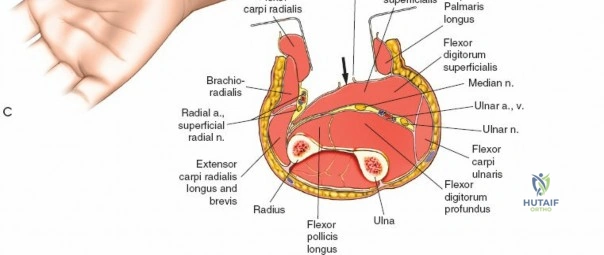

A thorough understanding of forearm anatomy is paramount for safe and effective fasciotomy. The forearm is typically divided into four primary osseo-fascial compartments, although some classifications may describe five:

- Superficial Volar (Flexor) Compartment: Contains pronator teres, flexor carpi radialis (FCR), palmaris longus, flexor carpi ulnaris (FCU), and flexor digitorum superficialis (FDS). The median nerve and ulnar artery course deep to this compartment, but their branches may be superficial. The fascia overlying this compartment is robust.

- Deep Volar (Flexor) Compartment: Deep to the FDS, this compartment houses flexor digitorum profundus (FDP), flexor pollicis longus (FPL), and pronator quadratus (PQ). The anterior interosseous nerve (AIN), a branch of the median nerve, and the anterior interosseous artery (AIA), a branch of the ulnar artery, are key structures here. The median nerve, deep to the FDS, is a critical structure that requires protection. The ulnar nerve and artery run along the ulnar border.

- Dorsal (Extensor) Compartment: Contains the extensor carpi ulnaris (ECU), extensor digiti minimi (EDM), extensor digitorum communis (EDC), and supinator. The posterior interosseous nerve (PIN), a branch of the radial nerve, courses through the supinator and then becomes the primary innervation for the dorsal compartment musculature.

- Lateral (Mobile Wad) Compartment: Also known as the mobile wad of Henry, this compartment contains the brachioradialis (BR), extensor carpi radialis longus (ECRL), and extensor carpi radialis brevis (ECRB). The superficial radial nerve runs deep to the brachioradialis in its distal third.

Release of Dorsal Compartment: Identify the investing fascia over the extensor muscle group (ECU, EDM, EDC, supinator). This fascia is incised longitudinally throughout the length of the incision. Ensure full decompression of all muscle bellies.

The dorsal fascia is incised here, allowing the extensor muscles to expand. The extensor digitorum communis and other dorsal muscles are visible.

Release of Mobile Wad (Lateral) Compartment: This compartment contains the brachioradialis, ECRL, and ECRB. The fascia overlying these muscles should also be released through the dorsal incision, often by extending the fascial release more radially. The superficial radial nerve runs deep to the brachioradialis in its distal third; care must be taken to avoid injury during distal extension of the fascial release.

This image illustrates the release of the mobile wad, specifically showing the decompression of the brachioradialis. The full extent of the fascial release should be visualized.